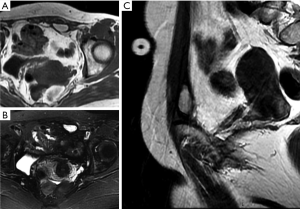

Desmoid-type fibromatosis is a relatively rare fibroblastic proliferative disease, previously referred to as aggressive fibromatosis or desmoid tumors. These tumors do not metastasize, but relapse can easily occur after surgical treatment. In some studies, desmoid-type fibromatosis has been described as the most common soft tissue tumor in the abdominal wall (1,24); however, this may be because lipomas are not usually treated surgically and were excluded from the analysis. Typically, these tumors occur in young females aged 20 to 40 years, more frequently during the first year after childbirth (25). Arising from the aponeurosis of the abdominal wall muscle, desmoid fibromatosis usually occurs in the anterior abdominal wall and is usually located in the rectus abdominis, the internal oblique muscles, and the surrounding fascia. Due to the distinct location and tendency of these lesions to develop in women of childbearing age, they can usually be distinguished from other forms of deep desmoid-type fibromatosis.

On CT, desmoid-type fibromatosis usually appears as a round or oval, nonspecific soft tissue mass with a density similar to that of muscle. Generally, it does not grow across the midline and is significantly enhanced after contrast injection. It shows low-to-intermediate signal intensity (SI) on T1WI and high SI on T2WI. Internal band-like findings of low signal heterogeneity on all sequences are relatively distinct on MRI (Figure 4). These low-SI bands are common (62–91% of cases) in desmoid-type fibromatosis compared with other neoplastic lesions and are related to the collagenized and hypocellular band regions observed on gross pathological examination, representing fibrous and collagenized regions (26,27). Extension along fascial planes (i.e., the “fascial tail” sign) adds specificity for the diagnosis (Figure 3) (24,28). MRI is optimal for detecting deep intra-abdominal extension that, although unusual, is important for guiding complete surgical resection. High SI on T2WI has been shown to correlate with greater cellularity and an increased recurrence rate (29).